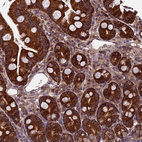

Immunohistochemical staining of human small intestine shows strong cytoplasmic positivity in glandular cells.